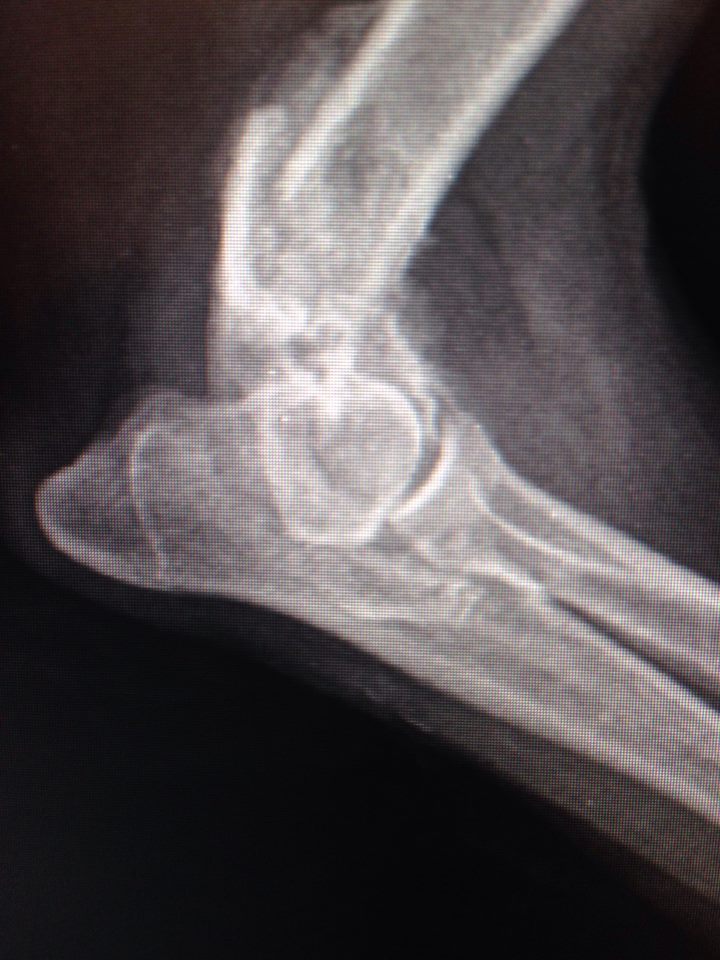

Вобщем все гораздо хуже оказалось.Только характер приятный,ласкавая.

Очень паршивый перелом.... сложная операция.

Не понятно куда и зачем одевали гипс.... зато стерилизовали.